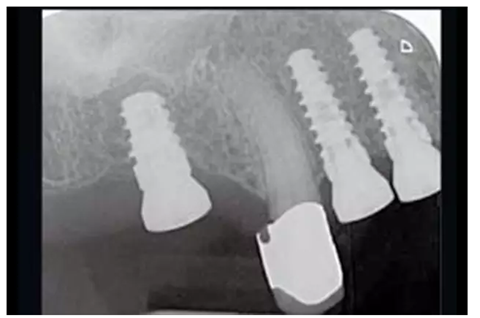

圖14:放置了3顆RatioPlant Avantgarde (HumanTech Germany)種植體。

圖16:種植后4個月,放射線檢查RatioPlant種植體的骨結(jié)合情況。

圖17& 18:Katharina Dietz-Epple醫(yī)生(Aalen, Germany)完成的冠修復(fù)(上頜)及可摘局部義齒修復(fù)(下頜)。